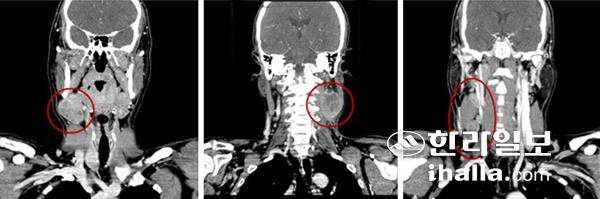

급성 감염에 의해 림프절의 크기가 증가됐을 가능성이 있다면 일단 약물치료를 시행한다. 소염진통제나 항생제 치료를 통해 급성 감염을 치료함으로써 원인 질환과 함께 림프절 종괴를 없애보는 것이다. 만약 단순한 약물 치료에 의해 크기가 감소될 경우에는 대부분 악성 질환의 원인을 배제할 수 있게 된다. 목 부위 림프절의 혹이 악성 종양의 전파에 의한 것임이 의심될 때는 우선적으로 세침흡입검사를 통한 세포학적 진단을 시행하게 된다. 세침흡입검사는 외래 진료에서 바로 시도할 수도 있고, 혹의 위치가 깊숙할 경우에는 초음파를 보면서 시행하기도 한다. 초음파 검사를 함께 할 경우에는 깊숙이 위치한 혹을 더욱 정확하게 검사할 수 있음과 동시에, 혹의 모양이나 주변 구조들과의 상관관계 등 임상적으로 필요한 영상 정보를 얻을 수 있어 유용하다. 악성 종양에 의한 것임이 확인되면 컴퓨터단층촬영(CT)을 통해 보다 상세한 영상 정보를 획득할 수 있다. 결핵에 의한 감염이 의심될 때는 세침흡입검사를 통해 얻은 림프절 세포에서 결핵균의 유전자를 확인하는 검사(Tbc-PCR)를 추가로 시행하기도 한다.